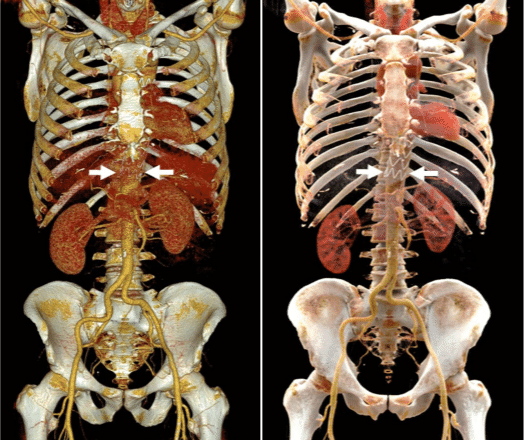

Volume rendering

Volume rendering is a computer graphics technique that creates 3D visualizations directly from 3D scalar datasets (like CT/MRI scans) by sampling the entire volume, rather than just surface data